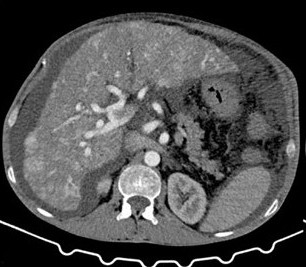

• Complex Intrahepatic Vascular Shunts in Hereditary Hemorrhagic Telangiectasia: From Portal Hypertension to High-Output Cardiac Failure

Filipe Nery, Diana Valadares, Manuel Teixeira Gomes

36-40

DOI: https://doi.org/10.60591/crspmi.557